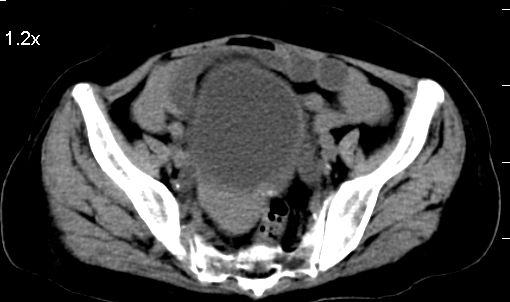

标题: CT10133:F、74岁,反复血尿10天。 [打印本页]

标题: CT10133:F、74岁,反复血尿10天。

膀胱充盈可,壁光滑厚薄尚均匀,其内下方可见不规则的致密影,建议做膀胱镜检查

膀胱癌突破浆膜可能性大

考虑膀胱癌可能性大伴双侧输尿管下端扩张.

膀胱后壁见不规则致密影,我们遇到这样的病人都再做一次俯卧位扫描;排出膀胱内凝血块。

1.膀胱后壁见不规则致密影,占位?膀胱内凝血块?建议俯卧位扫描、膀胱镜检查.

2.双侧输尿管下段扩张.

膀胱三角区不规整软组织改变,双侧输尿管扩张,所以占位性病变肯定首先考虑,建议改变体位扫描除外游离血块影,但老年人出血原因一定要查明。